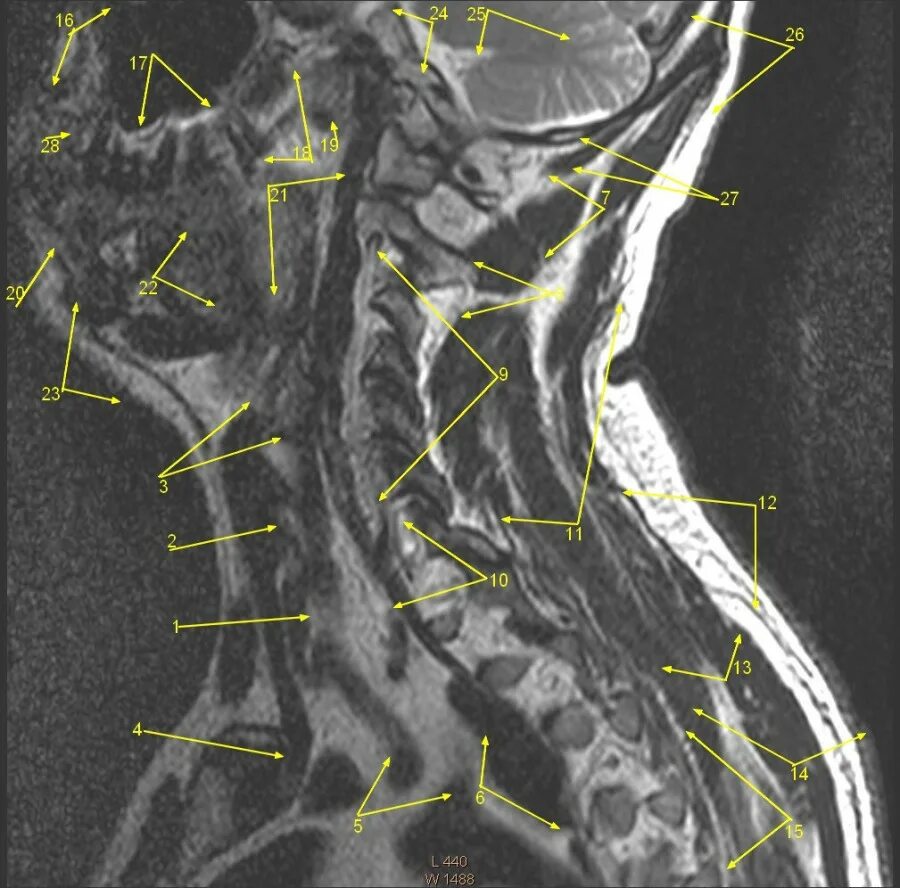

Сегменты вса мрт